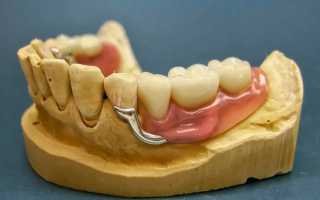

Бюгельный протез на челюсть, фото которого можно встретить для каждого конкретного вида, представляет собой съемную или несъемную конструкцию, в основе которой лежит использование бюгеля – специальной дуги из металла с закрепленными на ней элементами из пластмассы. В конечном итоге протез полностью имитирует внешне здоровую челюсть.

Металлический каркас позволяет создать и зафиксировать бюгельный протез только при наличии нескольких здоровых зубов. Основное преимущество полученной конструкции заключается в меньшей, чем у стандартного протеза, толщине. При этом литая форма исключает дискомфортные ощущения в процессе ношения.

Кроме непосредственно видов, отдельными типами выделяются способы крепления протезов:

| Вид | Описание |

| На телескопических коронках | Для этого требуется сточить опорные зубы и установить на них коронки, которые будут удерживать конструкцию. |

| На кламмерах | Приспособления внешне выглядят, как крючок, который цепляется за 2 крайних опорных зуба на 2/3 их окружности. |

| На замках-аттачменах | Конструкционно они похожи на кнопочные механизмы, которые соединяют опорные зубы с протезом. |